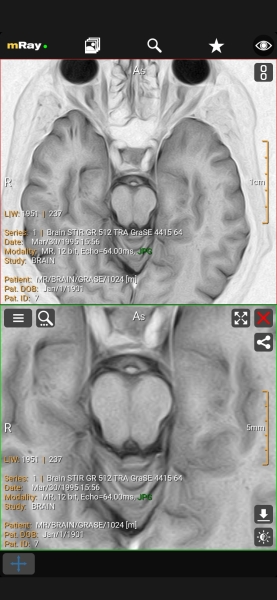

mRay

Ещё одно функциональное приложение, которое имеет всё необходимое для просмотра результатов обследования, включая измерения, пометки в виде текста и фигур, а также выделения областей. mRay бесплатно и не содержит рекламы, но требует регистрации по почте (можно через временный ящик).

С помощью жестов изменяйте контраст и масштабирование, а через расширенное меню выбирайте вспомогательные инструменты и настраивайте параметры.